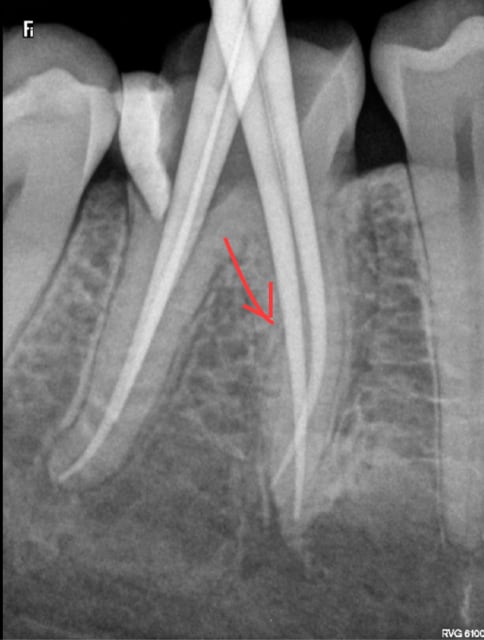

Ce qui m'intrigue, c'est qu'une aiguille est beaucoup plus radio opaque (blanc plus franc sur la radio), et en effet, ton axe, chicot, n'est pas celui utilisé habituellement !?!

Ben si mais c'est pas l'axe de l'image que j'ai utilisé. 30 °c'est dans le sens vestibulo lingual pas mésio distal ! Et l'aiguille je l'ai enlevée !-)